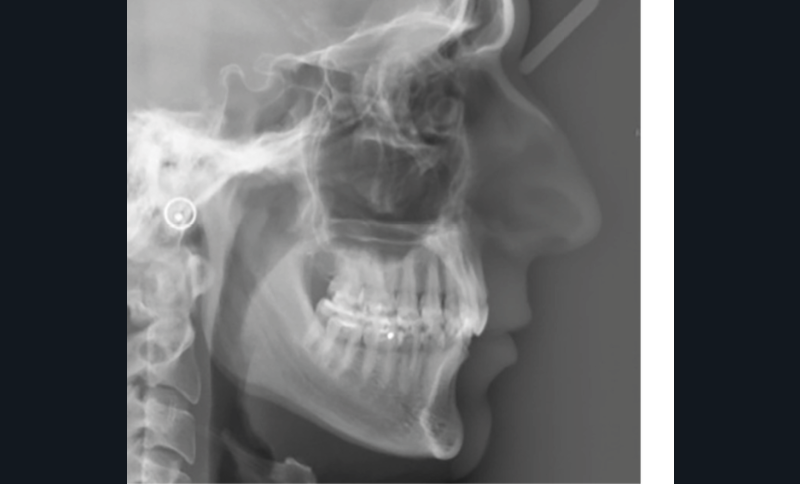

Examens complémentaires (fig. 3)

La téléradiographie de profil et l’analyse céphalométrique montrent une classe I squelettique tendance classe II dans un contexte d’hypodivergence, caractéristique des classes II division 2 [3,4]. L’axe de l’incisive mandibulaire est correct, au sein d’une symphyse épaisse, tandis que l’incisive maxillaire présente une rétroalvéolie importante. La supraclusion antérieure est d’origine mixte, majoritairement mandibulaire, en lien avec une courbe de Spee marquée.